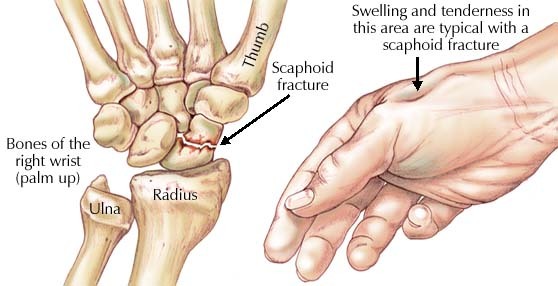

- 우선 주상골(Scaphoid)은 손목뼈에서 요골쪽에 위치한 뼈입니다.

- 코담배갑부위(Snuff box)에 누르면 통증이 있는 증상이 가장 흔합니다. 그리고 손에 힘의 약화를 느낄 수 있습니다.

- 손목이 부어있거나 멍이 생기는 경우는 골절과 탈구가 동반된 심한 경우에 볼 수 있고, 대부분의 경우는 증상이 별로 심하지 않습니다. 이 때 주상골을 직접 눌렀을 경우 통증을 호소하는 경우가 많습니다.